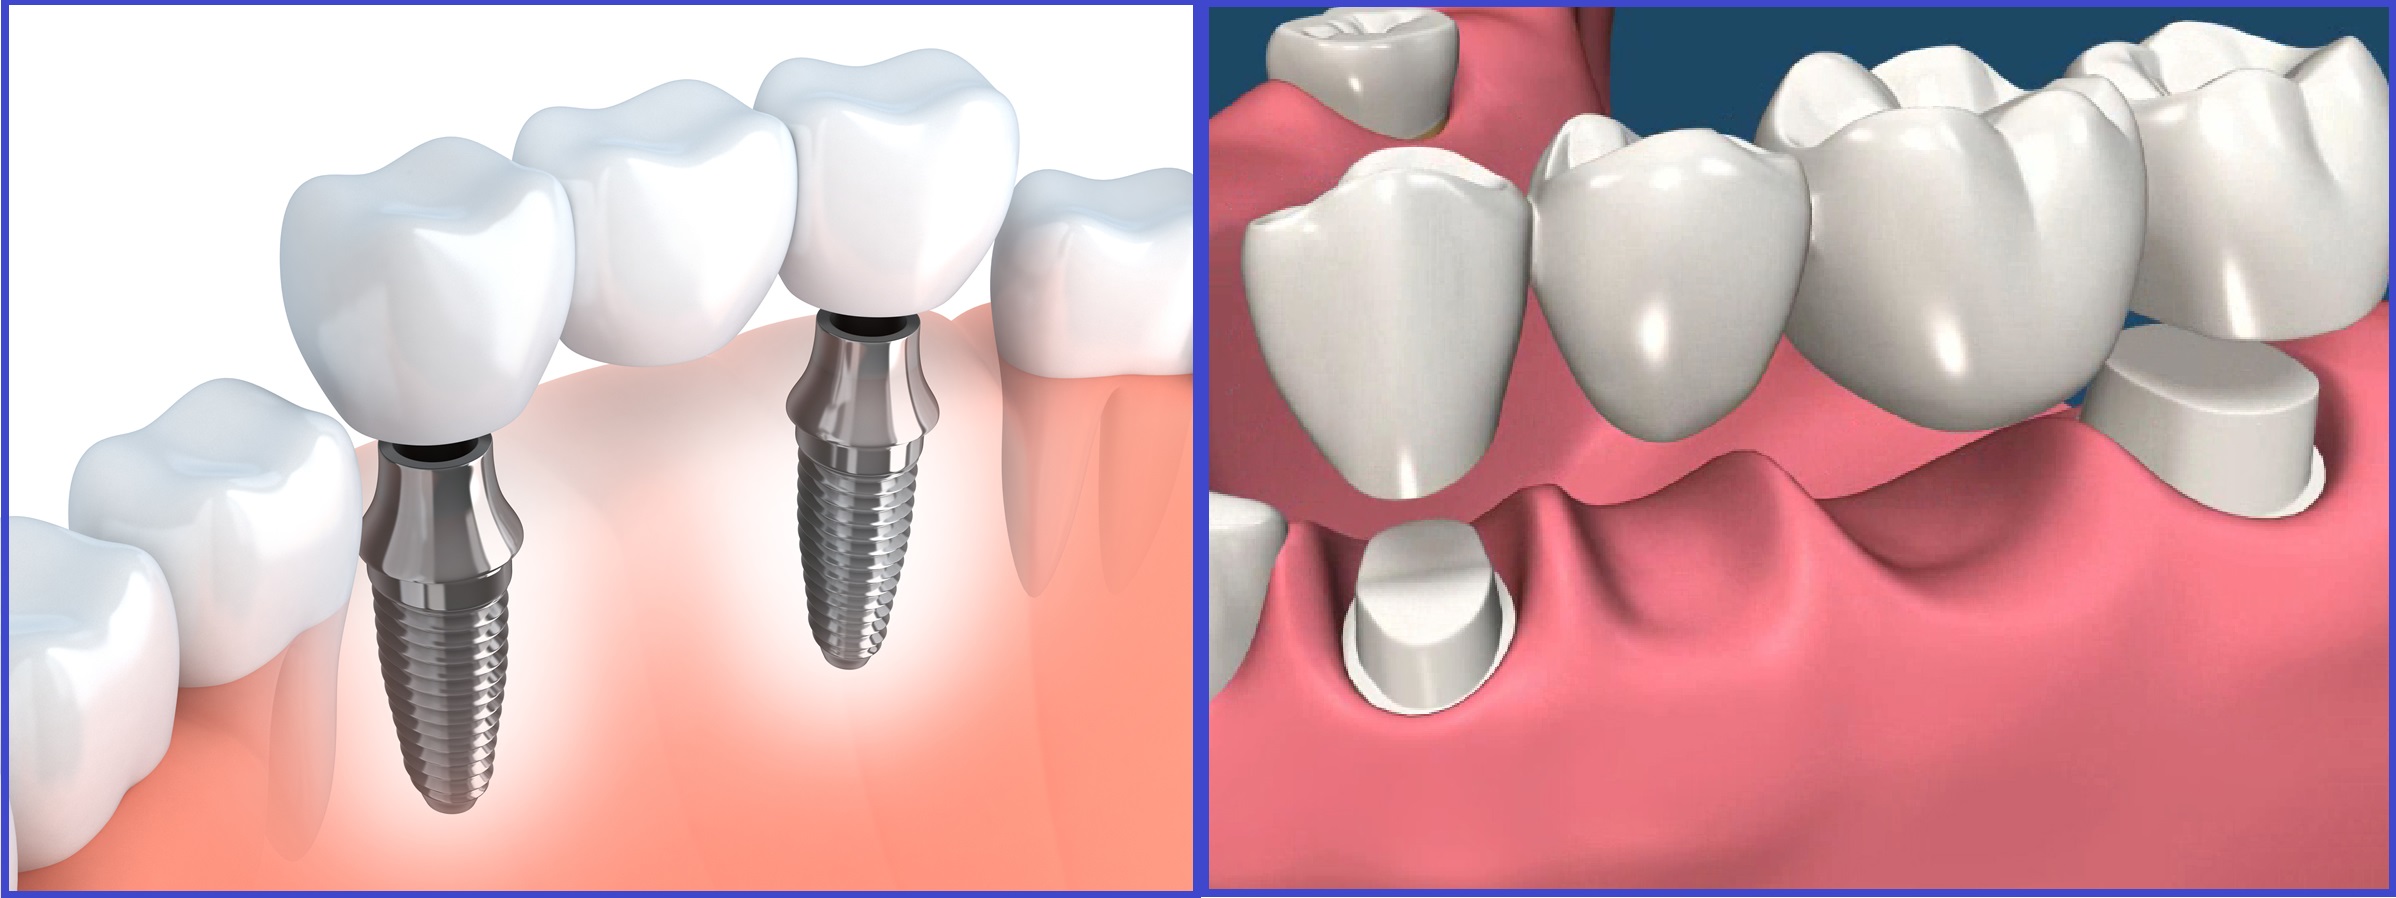

Soluzione per la perdita di un singolo dente